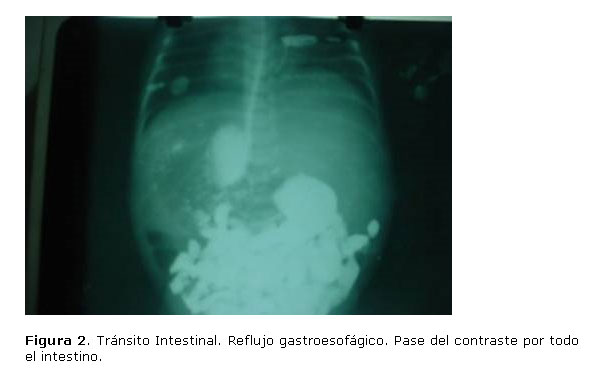

Durante este período se mantiene con una cobertura de antibiótico de amplio espectro Ceftriaxona (100mg/kg/dia) y Meronem (20mg/kg/d) y adecuado aporte hídrico, hasta que en la medida en que se empezó a reducir el contenido gástrico y aparecen ruidos hidroaéreos con buena peristalsis intestinal se inicia alimentación por gastroclisis continua hasta que se comprueba por un tránsito intestinal que hay buena evacuación con signos sugestivos de gastritis y reflujo gastroesofágico grado III, iniciándose medidas para su resolución y empezar  el amamantamiento (figura 2.).

bbbbbb